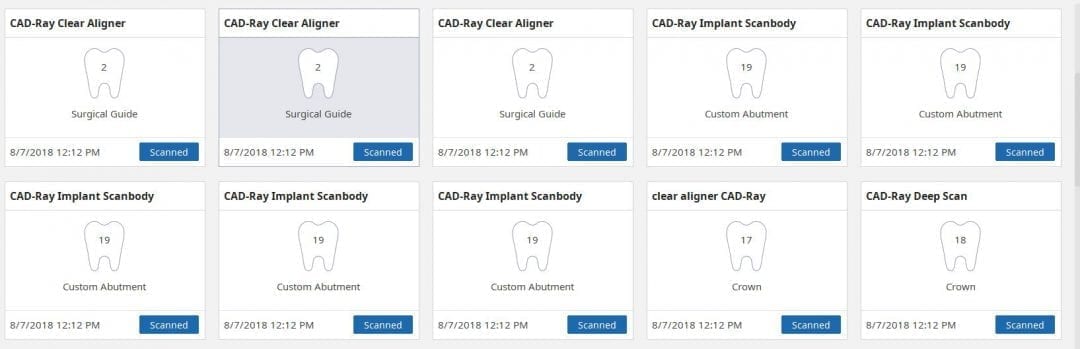

Checking Occlusion with Digital and Clinical Landmarks for a Clear Aligner Case

August 15, 2018Here’s a clear aligner case where the upper and lower arches were scanned and the buccal bite was taken with the Medit i500 IOS system. Prior to the digital impressions, […]